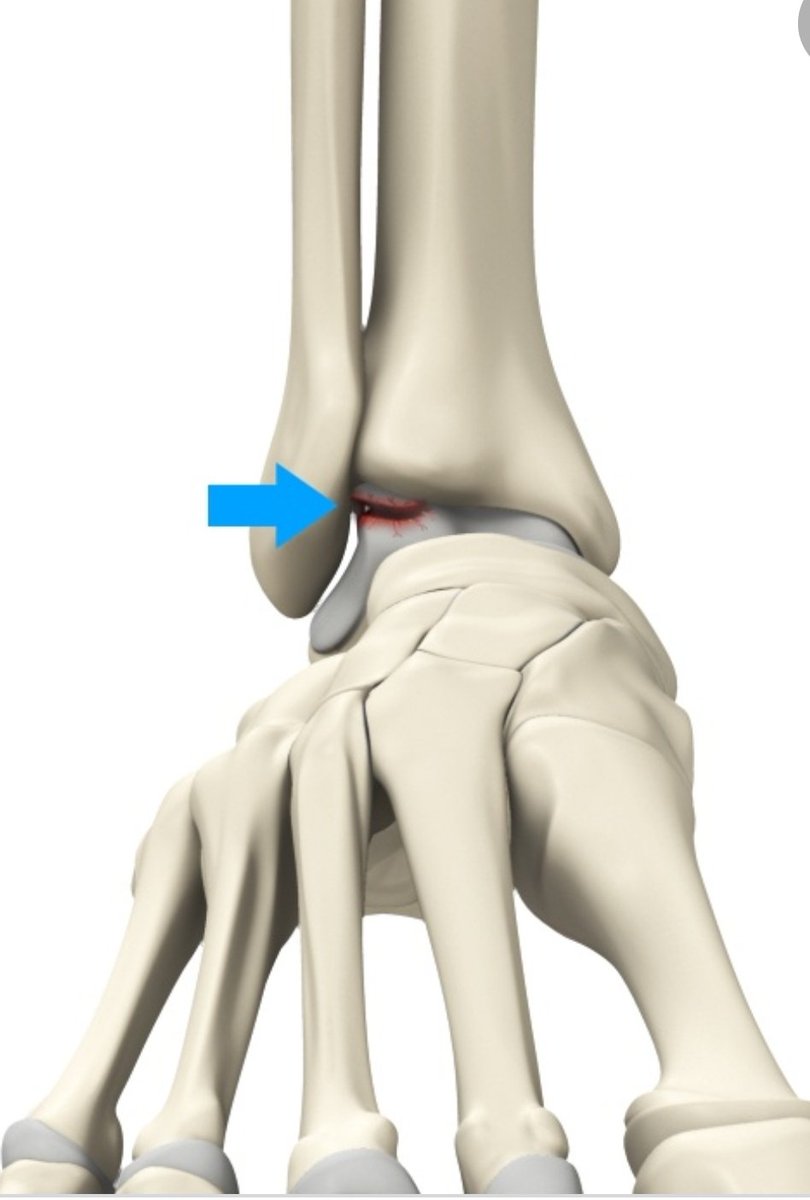

الأسباب:

كسور القدم والكاحل

التواء الكاحل وإصابة الاربطة الجانبية للكاحل

عدم استقرار مزمن الكاحل

تشوهات القدم اللتي تؤدي الى تكرار التواء الكاحل